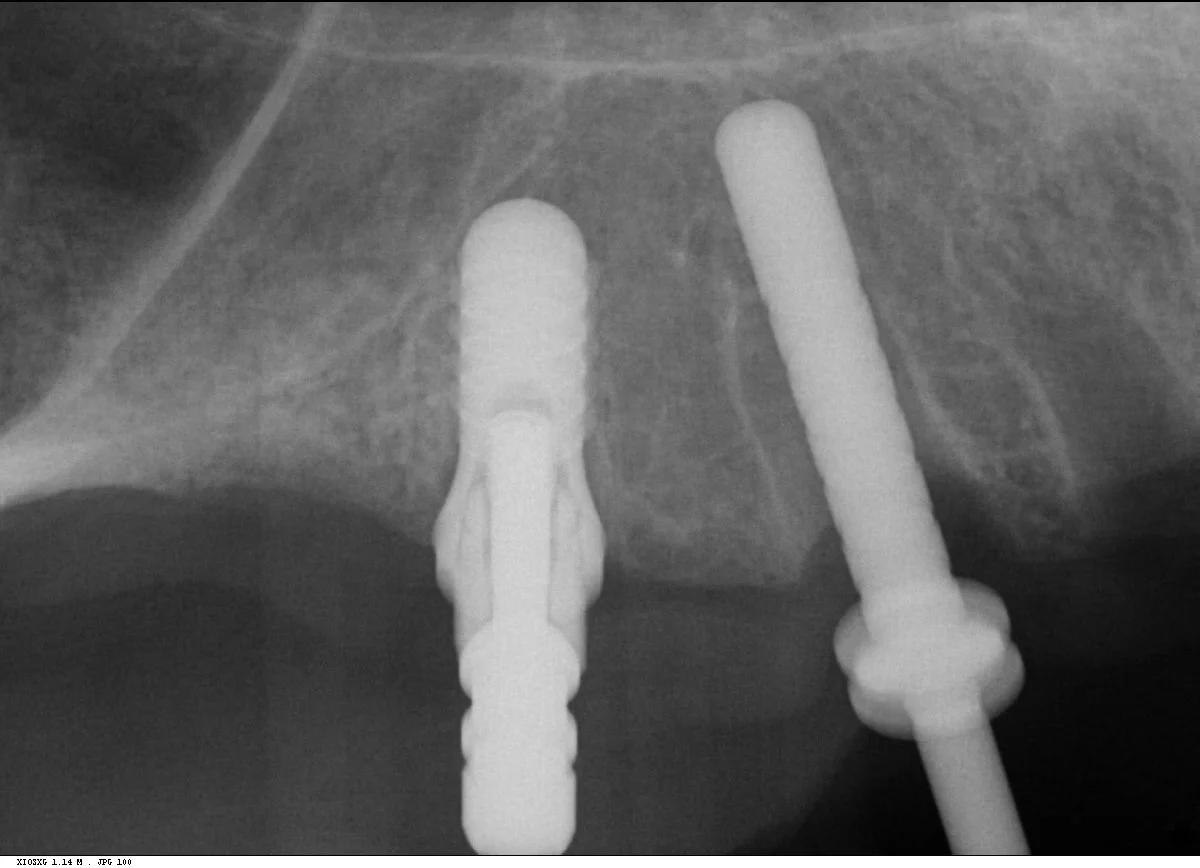

Multiple intra-operative radiographs were taken using depth gauges of gradually increasing diameter to ensure ideal positioning, particularly near vital structures such as the maxillary sinus. Following three months healing, definitive impressions were taken. Radiographs were taken to confirm complete seating of the impression copings prior to splinting of the impression copings and then impression taking.